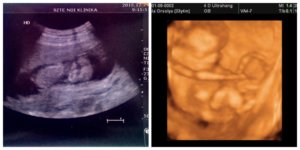

Egy héttel a kép elkészülte után született meg Sári

Ultrahangon a doki nálam vesemedence tágulatot állapított meg és mondta, hogy a babával minden oké. Nagyon örültünk, ez magyarázta a derékfájást és a lényeg, hogy a baba rendben van.